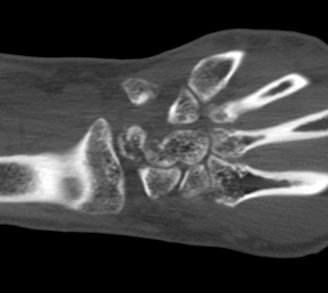

ÄÄÇ»ÅÍ ÃÔ¿µ :  ¿ù»ó°ñÀÇ ºÐ¼â°ñÀýÀÌ °üÂûµÊ(»çÁø 5, 6, 7, 8).